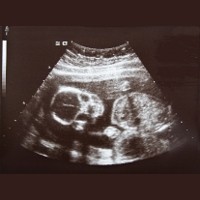

Saat mengalami cegukan, tubuh janin secara keseluruhan akan melompat ke atas dan ke bawah di dalam cairan ketuban. Jika cegukan terjadi saat dilakukan pemeriksaan, maka akan terlihat melalui ultrasonografi (USG).

Penyebab cegukan pada janin umumnya sebagai reaksi refleks saat menelan atau bernapas. Namun jika frekuensi cegukannya sering atau hampir setiap hari, ada baiknya memerlukan evaluasi USG karena ada kemungkinan akibat bayi mengalami masalah dengan tali pusarnya.

Satu hal yang harus dipahami ibu hamil adalah cegukan berbeda dengan kejang janin. Jika ibu hamil merasakan adanya gerakan yang teratur, berirama atau terjadi kedutan yang intens beberapa kali maka hal ini kemungkinan janin mengalami kejang. Untuk mengetahuinya bisa dilakukan pemeriksaan USG atau electroencephalogram janin.